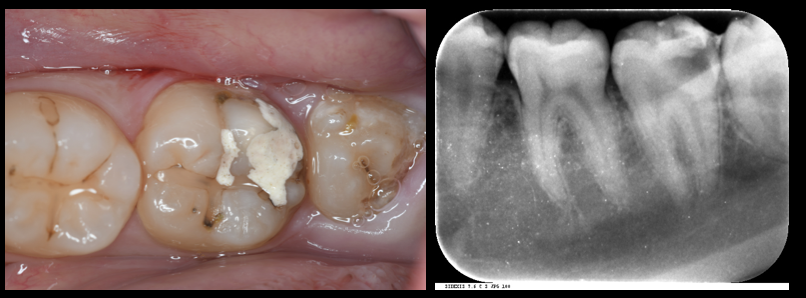

大きい虫歯ができてしまった患者さんの治療。

(左下7)歯の神経(歯髄)を保存したケース:(Vital Pulp Therapy:歯髄温存療法)をおこないCEREC:セレックを用いた即日オールセラミック修復をおこなったケース!!(自費診療!!)

(左下6)虫歯はダイレクトボンディングにて修復!!

写真左:術前の口腔内写真 写真右:術前のレントゲン写真